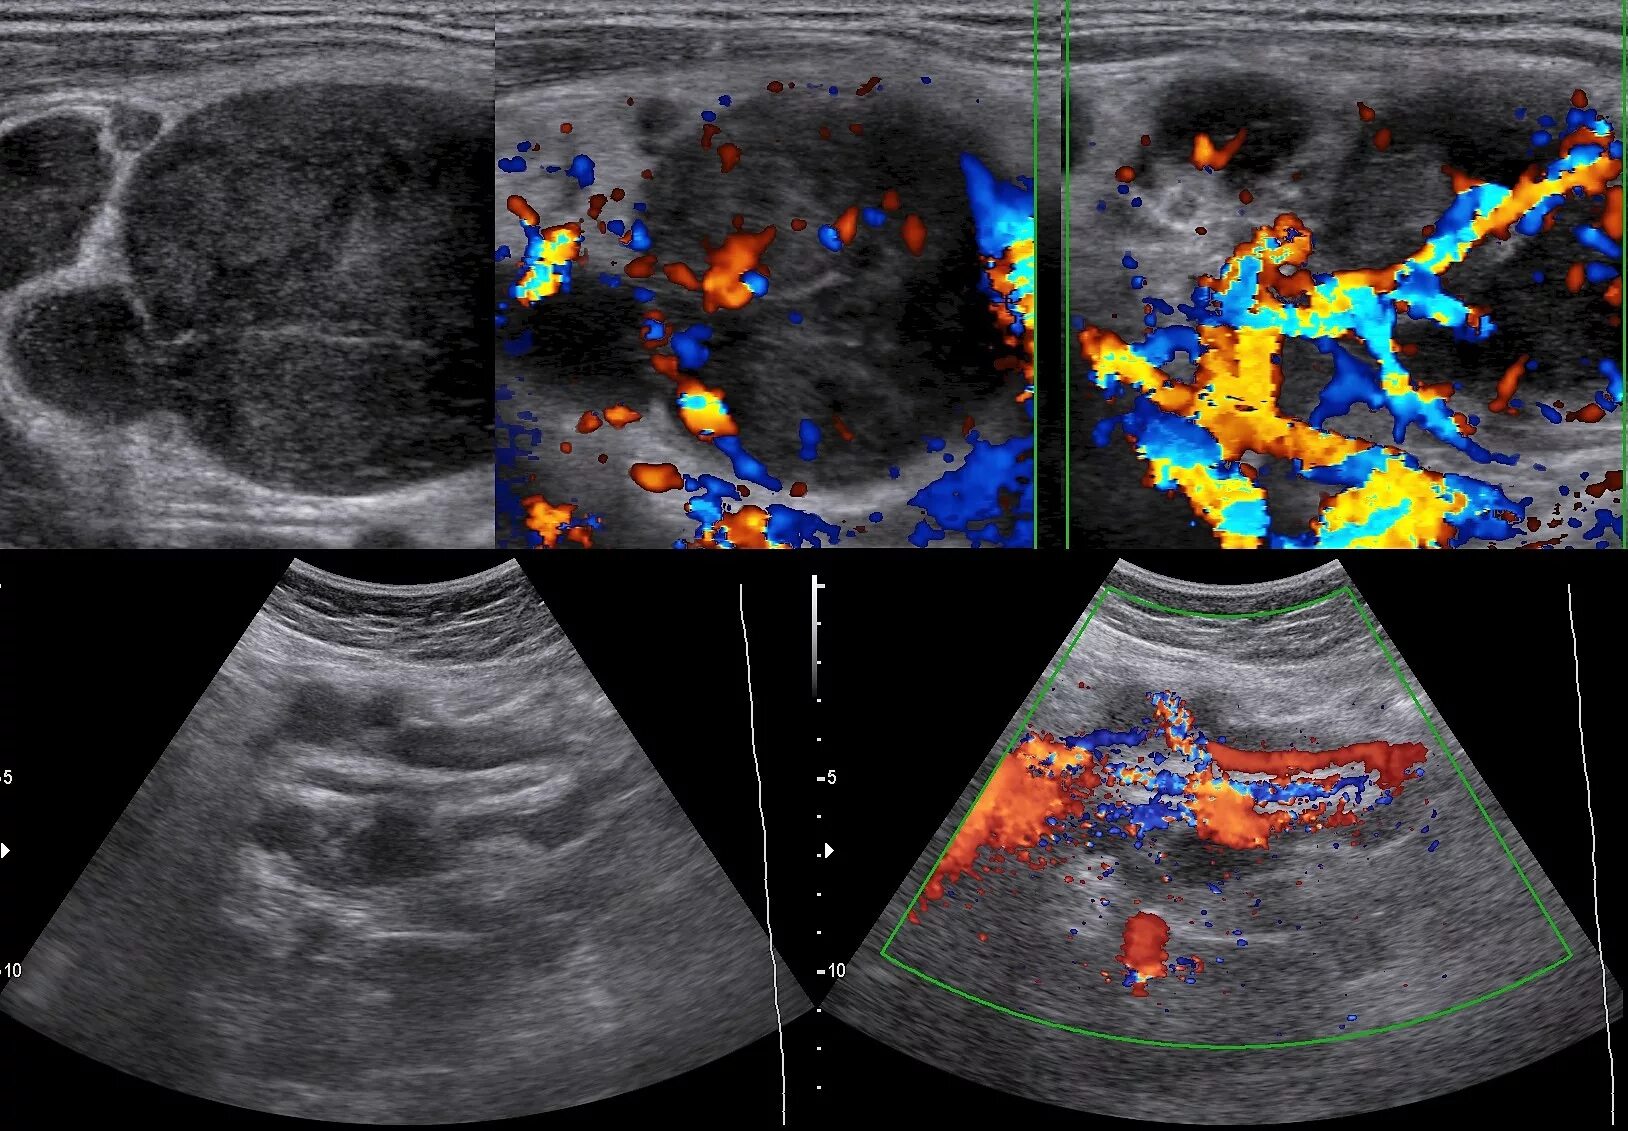

Обследование лимфоузлов